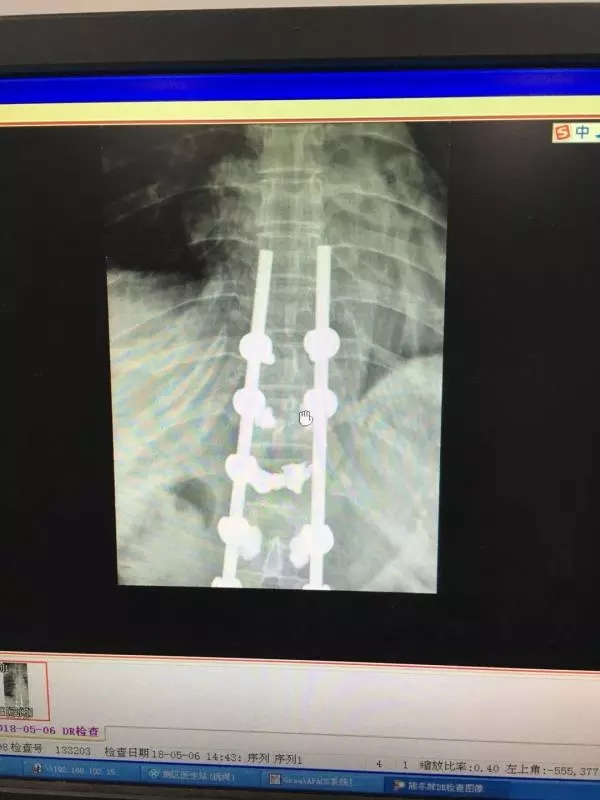

经皮椎弓根螺钉同样也是通过经皮做一小切口,利用C臂机作为医生的眼睛,依次进入导针,扩孔,后期进入椎弓根螺钉。操作稍有不慎,螺钉就可能进入椎管内,造成截瘫。如下图所示: